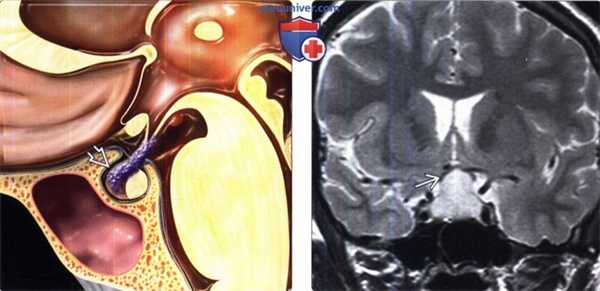

(Слева) На рисунке коронального среза показана физиологическая гиперплазия гипофиза. Железа равномерно увеличена в размерах и имеет слегка выпуклый верхний край.

(Справа) МРТ, постконтрастное Т1-ВИ, сагиттальный срез: у женщины 38 лет, которой проводилось лечение по поводу бесплодия, с жалобами на головную боль определяется однородное контрастное усиление гипофиза вертикальный размер которого составляет 12 мм.

(Слева) На рисунке сагиттального среза показан лимфоцитарный гипофизит. Обратите внимание на утолщение воронки с исчезновением нормального ее сужения «сверху вниз», а также инфильтрацию передней доли гипофиза.

(Справа) МРТ, Т2-ВИ, корональный срез: у беременной женщина со зрительными и эндокринными нарушениями в селлярной/супраселлярной областях определяется гиперинтенсивное объемное образование, смещающее зрительный перекрест кверху. При хирургическом вмешательстве с целью декомпрессии зрительного перекреста был выявлен лимфоцитарный гипофизит Рентгенологическая картина имитирует макроаденому гипофиза.